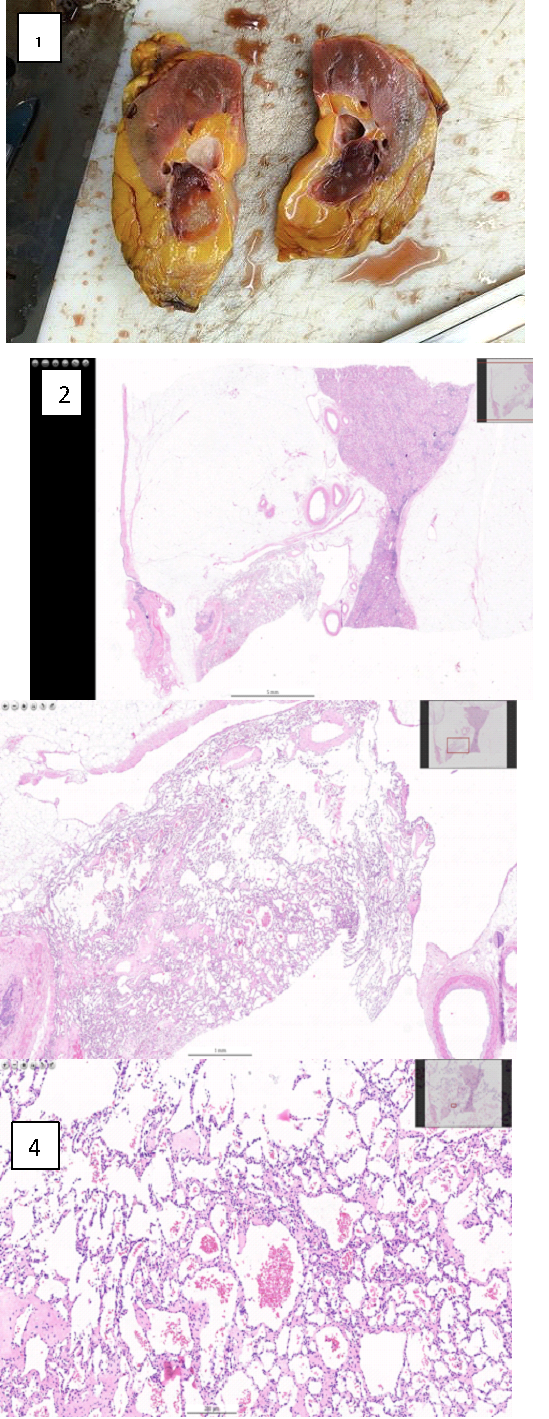

Figure 3 describes the macroscopical and microscopical characteristics of the operatic specimen.

Macroscopically, the nodule of 3.5×2.5x2.5 cm was located at the renal sinus. It resulted to be circumscribed but without a recognizable capsule and with a translucent red cut surface, which was extensively sampled (Figure 3.1).

The described sinus nodule had the histological features of AH. The epicentre of the lesion was in the renal sinus and microscopic contiguity with the apex of a renal pyramid is observed (Figure 3.2, Figure 3.3, Figure 3.4).

Figure 3

Figure 3: Macroscopical and microscopical findings. 1) Macroscopic appearance of the AH of the renal

sinus. 2) Magnification 10x. 3) Magnification 40x. 4) Magnification 200x.